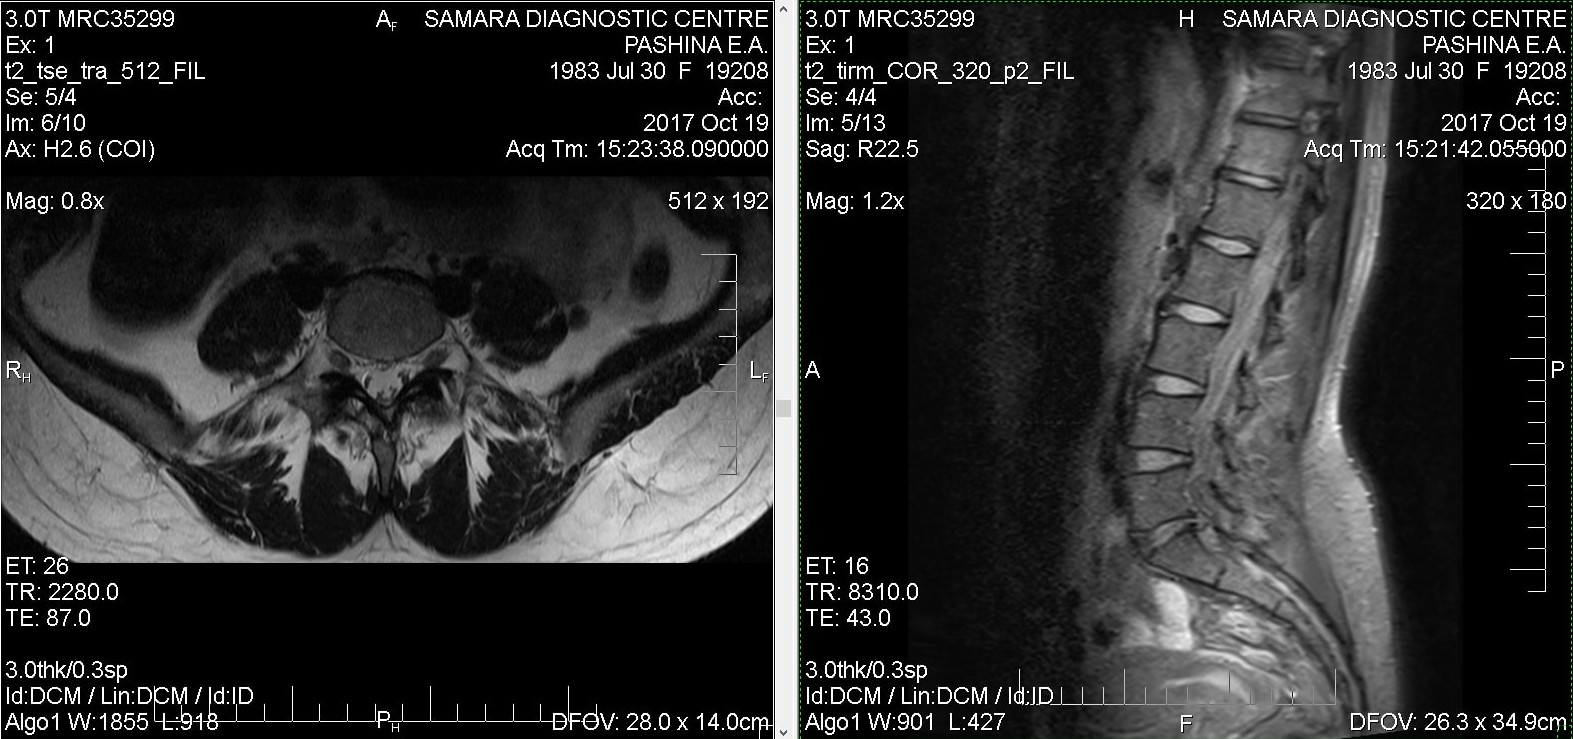

Тренировки с межпозвоночной грыжей.